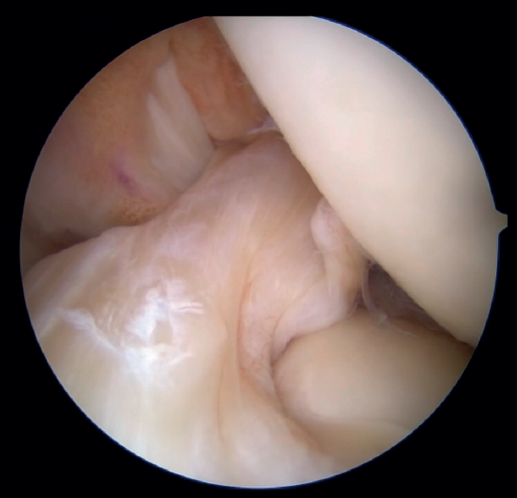

The patient is placed in the supine position and the leg is draped and prepared for knee arthroscopy at the surgeon's discretion, as if an ACL plasty were to be performed. The anterolateral and anteromedial portals are established as usual, and the joint is explored. On exploring the central compartment, it should be confirmed by direct vision and also palpation that the lesion is proximal and that the tissue quality is good; if the tissue is friable and tears easily, repair is not indicated. If the ACL remnant is attached to the PCL, it must be dissected so that the ACL is free and can be manipulated to its insertion site. A blunt shoulder arthroscopy periosteotome is best used for this, although a synoviotome, vaporizer or plasma applicator could also be used, as long as care is taken not to break or burn the tissue and render it non-viable. If there are concomitant meniscal or cartilage lesions, they should be treated earlier in order to avoid forced varus and valgus positions after the repair is completed.

After having confirmed the proximal lesion of the ACL and the good quality of the remnant ligament tissue, and having treated any accompanying injuries in the other compartments, an accessory anteromedial portal is prepared. It is important to widely resect Hoffa's fat pad to improve vision, facilitate passage of the threads, and prevent the latter from adhering to soft tissues. A cannula, ideally flexible (PassPort® from Arthrex), should be used to prevent the threads from adhering to the soft tissues, although this is not essential. The use of long cannulas, such as shoulder cannulas, is not ideal, as they extend too far outside the skin and greatly restrict use of the instruments.

Once a good view of the central compartment is obtained, the area of the femoral footprint of the ACL is prepared to leave exposed bone, and microperforations are made in the medial wall of the lateral condyle to leave a bleeding bed to favor healing of the ligament (Figure 3). These microperforations can be made using specific instruments or with the implant punch. The advantage of using the punch is that the implant insertion site can be prepared at the same time, and only one instrument is used for the entire process (Figure 4). This step can be done after the suture has been prepared in the ligament, although doing it beforehand avoids the threads from standing in the way. The ideal point for fixation is just anterior to the native ACL footprint, although if the tear is partial or corresponds to Sherman I, it can be taken to the anatomical footprint without difficulty.